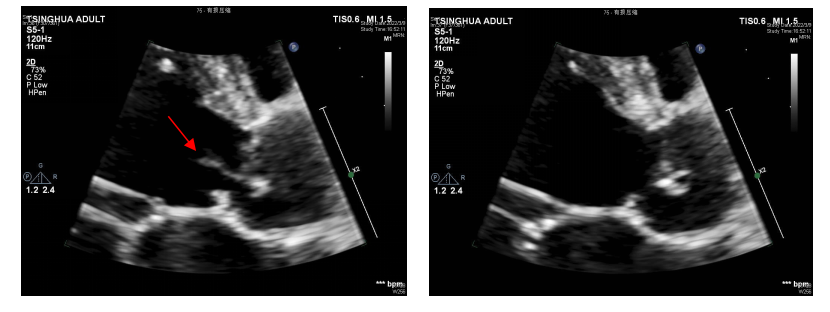

男性患者,58岁,因反复发热2周就诊。2周前,患者无明显诱因出现发热,为驰张热,最高体温39℃,无寒战、咳嗽咳痰、头晕头痛、腹痛腹泻、尿频尿痛等不适,无胸背痛、喘憋、呼吸困难、心悸、大汗等不适。就诊附近医院化验白细胞升高,口服头孢抗生素,体温降至正常后停药,2天后再次出现上述发热情况。再次就诊时检查胸部CT时发现胸主动脉增宽,未见明确肺部感染征象。进一步行主动脉CTA发现Stanford B型主动脉夹层(如图1)并收治入院。入院后超声心动图检查,提示主动脉瓣占位(赘生物不除外)、重度关闭不全(如图2-A,B,C);血培养发现星座链球菌,考虑感染性心内膜炎,瓣膜赘生物形成。

(图2-A,B)主动脉瓣可见赘生物,舒张期脱入左室流出道。

(图2-C)主动脉瓣大量返流

心脏超声:左室舒张末径63mm,左室收缩末径49mm,LVEF:54%。主动脉瓣三瓣叶,均毛糙,其上探及数个不规则条索样回声,长约13-26mm不等,随心动周期摆动,舒张期脱入左室流出道,致瓣膜闭合不全,主动脉瓣瓣大量返流;二尖瓣前叶瓣尖略增厚、回声增强,瓣叶开放尚可,关闭欠佳,二尖瓣少量返流;余瓣膜形态及结构未见异常。结论:1、主动脉瓣占位,赘生物可能性大,重度关闭不全;2、左心室增大,室间隔增厚;3、二尖瓣少量返流;4、左室整体收缩功能减低